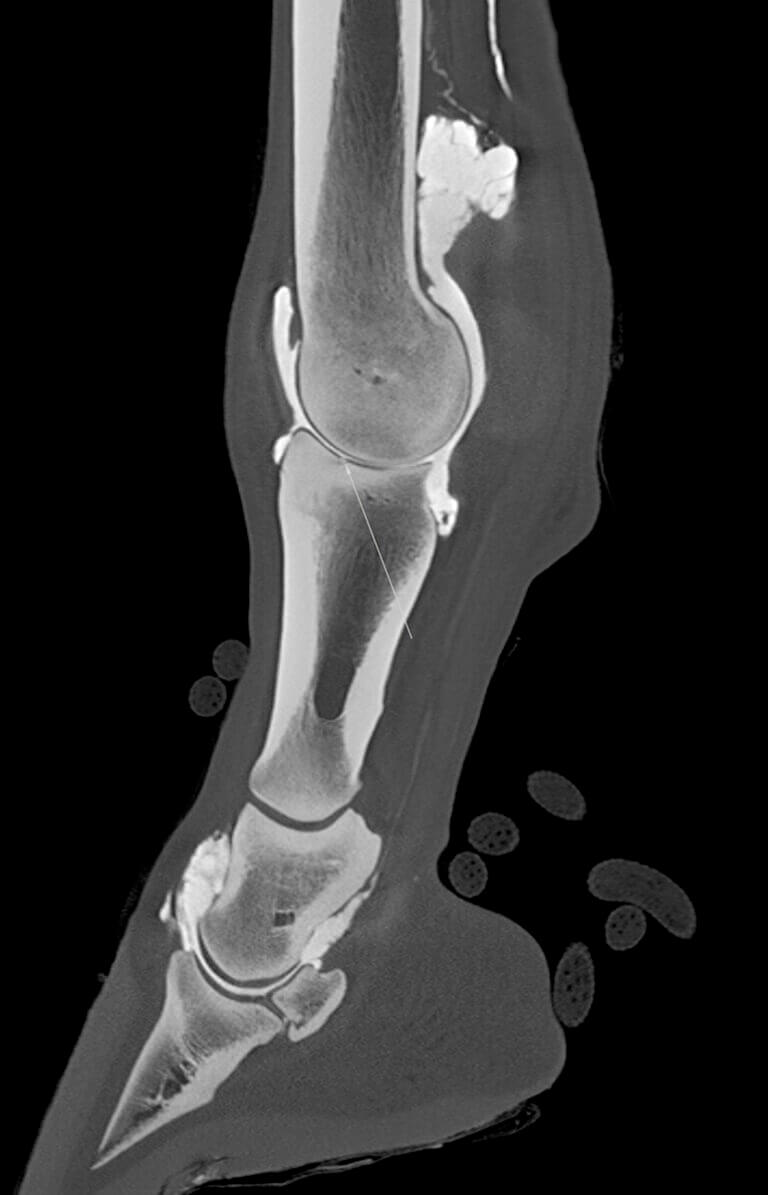

Bringing the Most Advanced Diagnostic Imaging to Equine Athletes